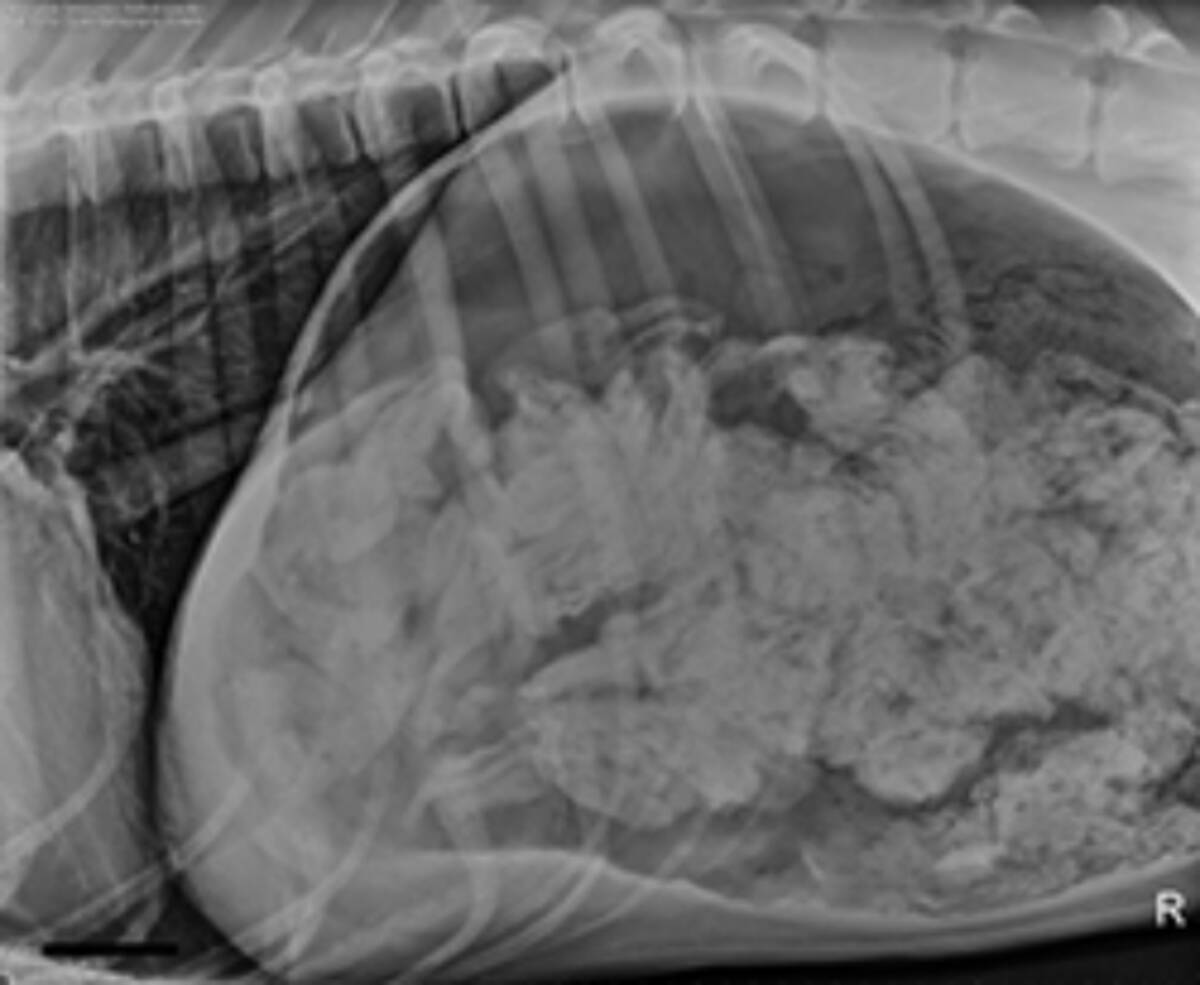

繁殖犬ボランティア体験記・レントゲンで胎数確認(犬の妊娠検診・最終回) ボランティア体験記録 koinu365 ツイートトイプードルレッド妊娠犬、出産予定1週間前のレントゲン写真 (12/04) トイプードルレッド妊娠犬の出産予定日10日前のレントゲン写真 (12/02) トイプードルレッド犬の出産、予定日よりも6日早く (11/04)妊娠 検査①(交配30~35日目) 超音波検査・・・妊娠しているかどうか 検査②(交配55~60日目) レントゲン検査・・・赤ちゃんの数、逆子かどうか、

レントゲン撮影 (犬の妊娠出産記録21) 11年09月10日 16時46分26秒 | 犬の妊娠出産子育て記録 昨日、お腹に何頭いるかを確認するため、動物病院でレントゲン撮影した獣医師監修 犬がレントゲン検査をするのはどんな時 費用と体への影響まで Docdog ドックドッグMixi犬の妊娠、出産、仔育て 出産前のレントゲン 我が家のオーストラリアン・シェパードが11月日頃に出産予定です。 胎動も激しくなり赤ちゃん達は元気そう! 頭数確認の為にレントゲンを撮ろうと思うのですが そろそろ撮っても大丈夫でしょうか?

レントゲン撮影時期 妊娠中のシャンプー ルナ さん犬もそんなに変わらないと思います。 ワンちゃんのそばで飼い主さんがタバコを吸っている方がよっぽどやばいと僕は思います。 re:妊娠のレントゲンについて パピ さんレントゲン撮影は出産直前である方が望ましい です。 逆に出産予定日から10日とか日とか 離れすぎているとレントゲン撮影の意味が薄くなります 。 なぜなら犬の胎児は妊娠末期に 急激に大きくなるんです。 だからなるべく出産予定日に近い方が